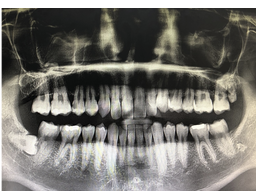

저는 사랑니가 네 개나 있었는데, 그 중에 두 개는 잘 자라서 별 문제가 없었어요. 하지만 나머지 두 개는 잇몸 안에 숨어있어서 치과에서 X-레이로 확인했어요. 그리고 그 두 개의 사랑니가 염증이 생겨서 아프기도 하고, 다른 치아에 영향을 줄 수 있다고 하더라고요. 그래서 치과에서는 사랑니를 발치하는 것이 좋다고 조언해줬어요.

사랑니 발치 과정은 이렇습니다. 우선 치과에서는 X-레이로 사랑니의 위치와 상태를 확인하고, 어떻게 발치할지 계획을 세웁니다. 그리고 마취 주사를 맞아서 아픔을 느끼지 못하게 해줍니다. 마취 주사는 조금 쓰리지만, 그렇게 아프진 않아요. 마취가 들어가면, 치과 의사님이 특수한 기구로 사랑니를 잡아당기거나 자르거나 해서 빼내줍니다. 이 과정에서는 힘이 들어가기 때문에 약간의 압박감이나 소리가 날 수 있지만, 아픔은 없습니다. 발치가 끝나면, 출혈을 막기 위해 거즈를 깔아주고, 어떻게 관리해야 하는지 설명해줍니다.